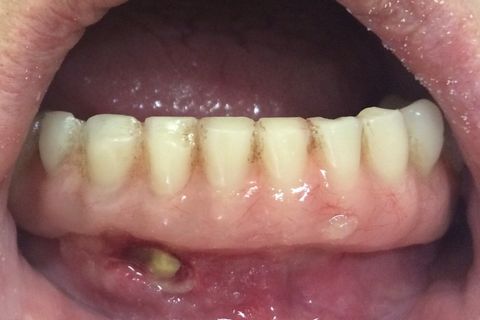

Aspecto da lesão

Prótese completamente infectada

Ausencia total de higiene